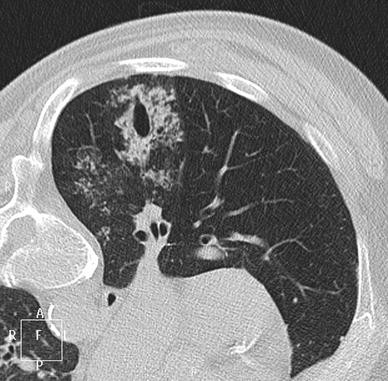

A 67-yr-old woman with a multinodular goiter who underwent surgery for a total thyroidectomy presents with blood coming out of the endotracheal tube after intubation. A) The thoracic computed tomography (CT) scan (coronal reformation) shows ectasia of the subsegmental B8 bronchus (9 mm in diameter) surrounded by ground-glass opacity in the right inferior lobe. B) The thoracic CT scan (axial oblique reformation) shows the length (40 mm) of the acquired ectasia of the subsegmental B8 bronchus abutting the pleural surface

In the first case, a 4-mm diameter stylet caused the rupture of a 3.4-mm diameter subsegmental bronchus. As the patient had no symptoms, she received no specific treatment and was discharged from the unit after three days. A CT scan performed one month later showed complete resolution of the bronchial injury and the pulmonary hemorrhage.